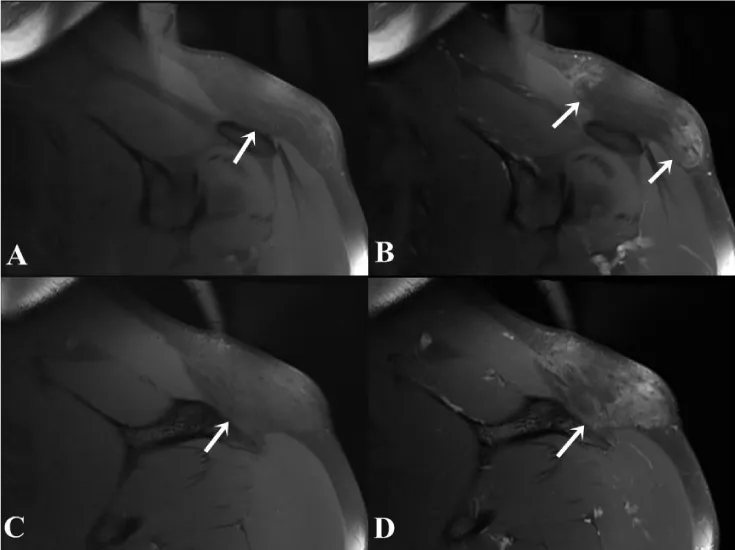

A 35-year-old male patient admitted to hospital with the mass growth on the left shoulder within 1 year. The patient complained of pain spreading from the lesion location to the left arm for the last 3 months. Physical examination revealed a rubbery and fixed lesion within 8x7 cm diameter on the left shoulder. A mild erythema was established on the skin without any varicose dilatation. US examination showed a large heterogeneous isoechoic lesion according to fatty tissue in the subcutaneous location. The solid lesion was in distinguishable from the adjacent muscle-fatty plans. MRI study revealed a solid lesion on the left shoulder within 27x68x92 mm diameter that had heterogeneous isoechoic character according to the fatty tissue on both T1- and T2-weighted imaging and fat suppressed technique showed suppression. The lesion had band shaped hypointense content. After the contrast material administration, fat saturated T1-weighted imaging demonstrated band shaped hypointense areas within the lesion were enhanced. The borders of the lesion were indistinguishable from normal fatty tissue in some regions (Figures 1,2). No evidence of any lesion was found in the adjacent bone tissue. The preliminary diagnosis of liposarcoma was considered after the imaging findings. The patient was operated under general anesthesia. In surgery, the lesion had no capsule and the borders were unable to separate from the surrounding fatty tissue. The mass with adjacent normal fatty tissue within 4x8x10 cm area were wide excised. The skin was primary sutured and closed. Pathological examination result was uncapsuled fibrolipoma. The lesion weight was 928 gram. At follow-up, there was no evidence of residual-recurrence in the US control at the 6 months and patient complaints disappeared.

The radiologic features of subcutaneous location of fibrolipomas defined in the literature are heterogeneous intensity on both T1- and T2-weighted imaging according to fatty tissue, presence of suppressed areas in fat saturation, well bordered or thin capsule occurrence and presence of enhancing areas on post-contrast series [1,4-6]. In one of these cases, calcification within the lesion is present in the foci [6]. MRI findings of a fibrolipoma in the nuchal region are defined as just submucosal fatty tissue thickening [7]. Our case differs from the literature in that undistinguished from the surrounding normal subcutaneous fatty tissue in some areas of the lesion borders. Lipomas are usually encapsulated lesions whereas fibrolipomas may be uncapsuled [3]. In our case, MRI was unable to demonstrate the borders of the lesion in some areas. In surgery, the lesion was inconvenient to separate from surrounding normal fatty tissue. These findings describe the formation of the lesion without capsule. Liposarcoma, spindle cell lipomas, pleomorphic lipomas are in the differential diagnosis of fibrolipomas. Classically, MRI findings of lipomas are isointensity with fat in MR sequences and suppressed in fat-suppressed techniques, and usually do not retain contrast material. MRI findings of spindle cell lipomas are not characteristic.

MRI features of well-differential liposarcoma are wide lipomatous content more than 75% and non-lipomatous component in extended septa more than 2 mm diameter with irregular appearance and/or nodular foci. After contrast material administration, the extended septa demonstrate evident or moderate enhancement [1]. In our case, MRI revealed enhanced thick septas larger than 2 mm and nodular foci. The radiological preliminary diagnosis considered liposarcoma due to imaging findings.